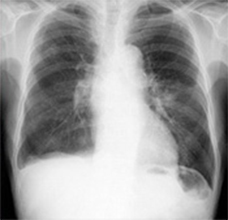

定期健康診断で検出された症例です。経時差分画像により、肺野外の病変異常に対しても変化を把握し易くなります。

正常患者を正常と言い切るのは診療上勇気がいるため、異常画像より読影時間がかかるという報告があります。経時差分の導入により、確信度が上昇し、読影時間を短縮できます。